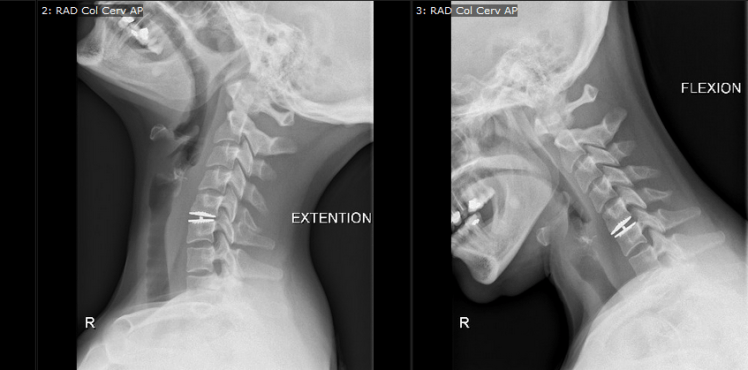

An arthrodesis of several cervical levels could limit the function of the cervical spine (flexion, extension, lateral flexion and rotations).

The cervical disc prosthesis maintains or restores the mobility of the adjacent cervical levels and therefore limits or avoids these problems.